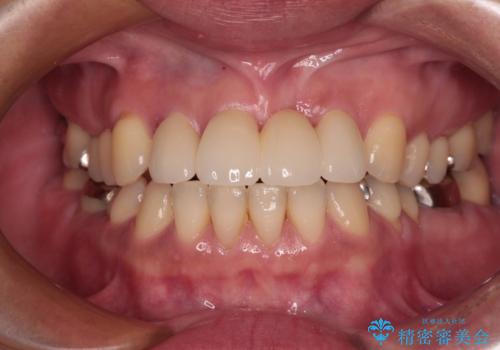

カリエールディスタライザーやワイヤー矯正を併用したことで、確実かつ短期間で治療を終えることができました。